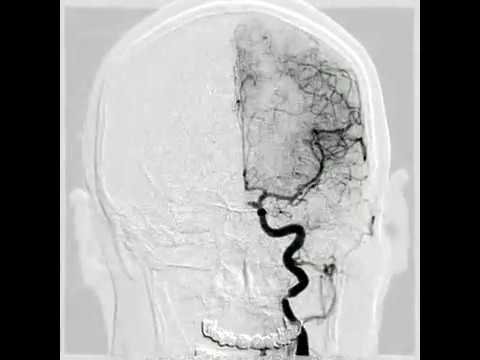

Hellow guys, Welcome to my website, and you are watching Recurrent BA Apex Aneurysm after Coiling & Flow Diversion Treated by Thrombectomy and Clipping. and this vIdeo is uploaded by Barrow Neurological Institute at 2023-04-27T16:38:22-07:00. We are pramote this video only for entertainment and educational perpose only. So, I hop you like our website.